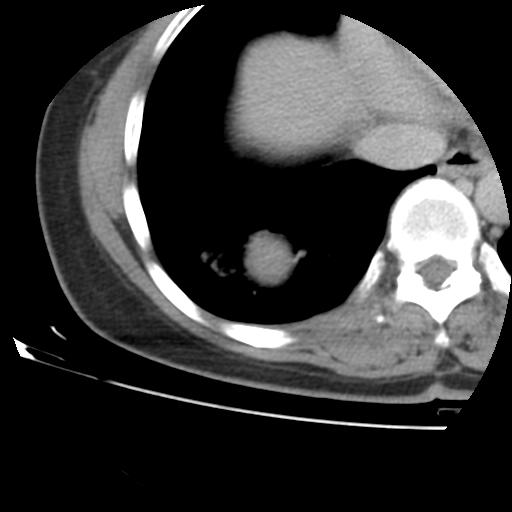

右肺下叶类癌

女 46岁,咳嗽咳血10月

【linyiming】右肺下叶见类圆形软组织影,边缘欠规整,略分叶状。考虑炎症假瘤可能?

未排除周围型肺癌。建议CT增强。

【心路寻觅】右肺下叶良性占位伴阻塞性肺炎,抗炎治疗后复查,不像单纯的炎性假瘤。

【刚起步】只有想不到的,没有长不到的。实性结节,强化明显,病人咳血,肺癌不能除外。

【aosangwa】肺癌的主要特征是:毛刺征、分叶征及胸膜凹陷征,此病例位于右肺下叶距胸膜很近,但没有胸膜凹陷征,其周围像示渗出性病变,病灶在两窗上没有大小没有发生大小改变。

考虑其良性肿瘤,炎性假瘤可能性大,其主要鉴别是:结核球、周围型肺癌、血管瘤

病理诊断类癌(周围型)。